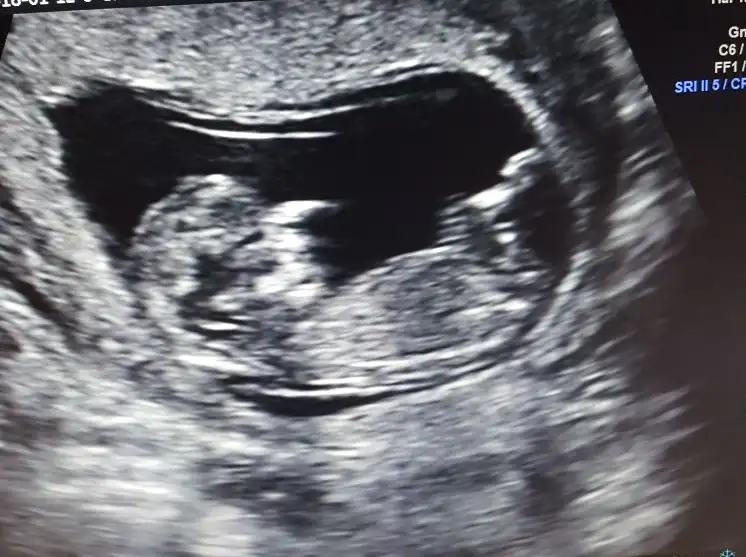

Gunaydinn kizlar bebegimi gördüm cok şükür .Biraz gergindim hic hareket etmiyordu .Dr rahatla dedi kendimi biraktigim anda hareketlendi :KK49:

Ense burnu normal ikili vermedim .

Hani dr 16 dan once cinsiyet soylemem de soylemem diyordu ya damardan girdim ikna ettim israrlarim uzerine tahminde bulundu az sonra foto atcam bir de siz bakin:emir_bebek:

Esim ekrandan cekmis elimizdeki net olmadi fazla

bu bebeiş aynı benim bebişime benziyor yapı olarak :dondurma: benimki kız bebişmiş acaba seninkidemi kız :halay:

Erkek dimi canim :KK15:

Kizlar da baksin da simdi söylersem gecersiz olur tahminler.Ben burdaki yorumlara da güvendiğim icin hemen soylemek istemiyorum .Ayyy cok heyecanli dr un agzindan zor da olsa laf aldim yaa daha bisey demem kiramadi .Ben cok kuralciyim olmaz falan filan derken soyleyiverdi:halay: